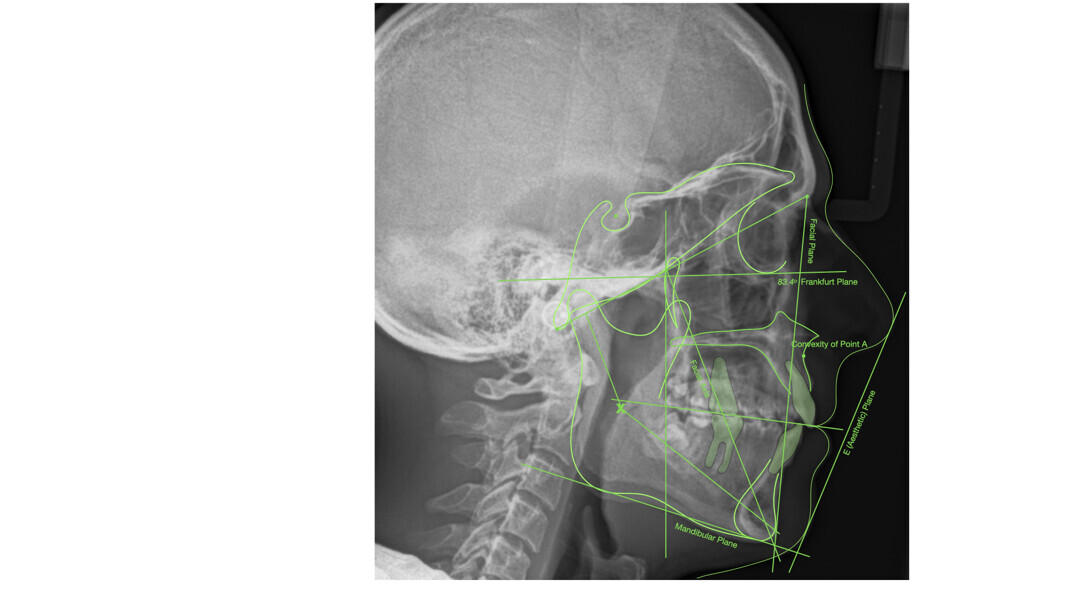

The cephalometric analysis showed a skeletal Class II malocclusion (convexity of Point A: 4.9 mm), a slightly retruded chin position (facial depth: 78.1°) and a skeletal open bite tendency (lower facial height: 53.19°; facial axis: 80.58°; Fig. 9). The mandibular incisors were lingually tipped (Li–APog: 9.3°) and retruded (Li–APog: 1.55 mm), and there was an increased inter-incisal angle of 142.9°.

Treatment results

The post-treatment extra-oral photographs showed the improvement of the smile aesthetics (Figs. 51–58). A solid bilateral Class I occlusion was achieved with normal overjet and overbite. The dental arches were well aligned and levelled, and even the severe rotation of the mandibular left second premolar was corrected with aligners only. The post-treatment cephalometric evaluation (Fig. 59) showed an improvement in the anteroposterior position of the mandibular incisors (Li–APog: 2.21 mm) while maintaining the facial height (lower facial height: 53.12°; facial axis: 83.96°; Table 1).

The panoramic radiograph showed that the root of the mandibular right lateral incisor had been uprighted by the HAT auxiliary, without any major root resorptions, while achieving good parallelism with the adjacent teeth (Fig. 60). The impacted mandibular third molars were still present because the patient refused to have them extracted.

A deviation analysis between the final clinical result and the initial situation was conducted to ascertain the extent of vertical movement in the posterior segments (Fig. 61). This was done to confirm the hypothesis that the relatively thick aligners would assist in bite closure by helping to intrude the posterior segments. The software used for this analysis was GOM Inspect Pro (Carl Zeiss GOM Metrology), which uses a highly accurate method of using optical metrology to measure deviations between two 3D data sets. The results confirmed intrusive movement of the molars and premolars, especially on the right side. The aggregate vertical intrusive movement was in the range of 0.5–1.0 mm. Conventional cephalometric tracings are unable to recognise movements of this order (Fig. 59).